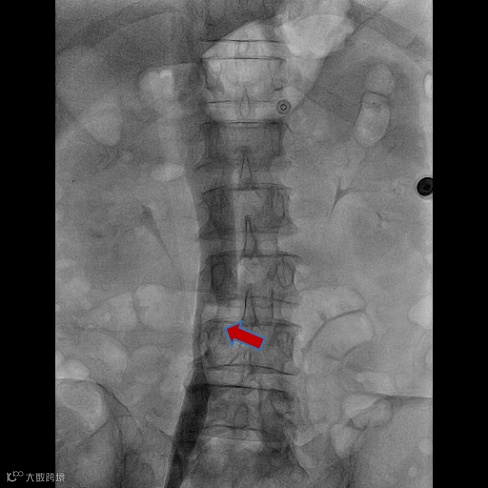

由沈阳市第一人民医院介入科陈建军主任团队运用中天天航™Pro血栓抽吸导管治疗一例急性左下肢深静脉血栓形成且伴有右下肢血流淤滞病变,成功清除血栓并快速恢复肢体灌注,欢迎大家阅读、分享、交流!

手术过程